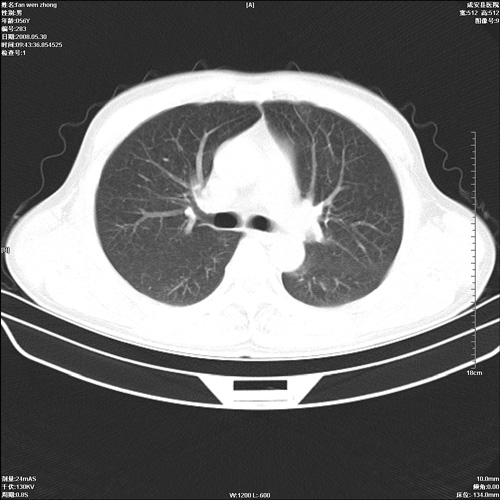

病人 男 56岁 一周前高热,体温达39-40度,经抗炎治疗后,体温渐降,达37,5-38度,轻微咳嗽,胸部不适 查白细胞为1.3万 行ct检查,请分析。

双肺内可见多发结节状病灶,并见小空洞,病人高热,白血球增高,应该是典型的迁徙性肺脓肿(多为金黄色葡萄球菌感染)。查一下口腔等其它部位有无感染灶。

双肺内可见多发结节状病灶,并见小空洞,病人高热,白血球增高,应该是典型的迁徙性肺脓肿(多为金黄色葡萄球菌感染)。建议治疗后复查.